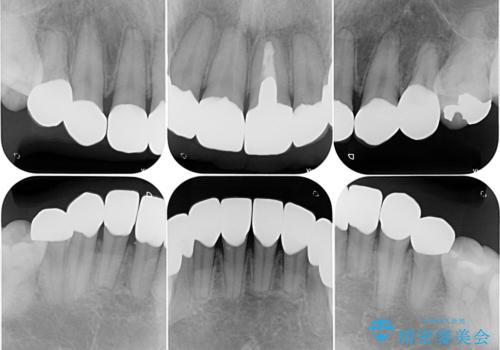

- 口元の突出感を改善するための抜歯矯正を終えた患者様ですが、幼少期からの変色した歯をセラミッククラウンにて自然な色合いに変えていくこととしました。

口を開けたときに目につく範囲を希望されたため上下ともに8本ずつをオールセラミッククラウンによる補綴治療を行うこととしました。

近年では大変珍しいですが、胎児あるいは乳幼児期の抗生物質の影響で永久歯が変色してしまうことがあります。

ホワイトニングでの改善は期待できないため、オールセラミッククラウンによる補綴治療が必要となります。